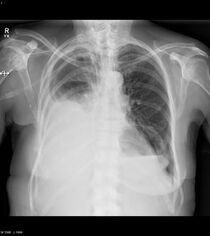

Breast cancer can metastasize anywhere in body but primarily metastasizes to the bone, lungs, regional lymph nodes, liver and brain, with the most common site being the bone.[4] Treatment of metastatic breast cancer depends on location of the metastatic tumors and includes surgery, radiation, chemotherapy, biological, and hormonal therapy.[5]